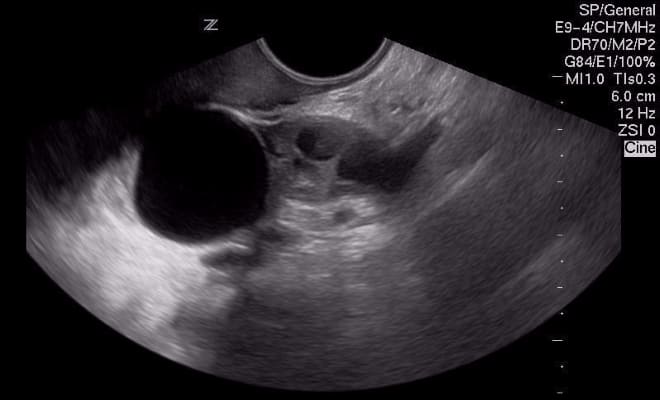

Вероятность перепутать кисту с беременностью во время УЗИ

Отличить оплодотворенную яйцеклетку от кистозного образования может даже врач-новичок. На ультразвуковом исследовании эмбрион становится видимым уже на третьей неделе беременности, а его сердцебиение можно услышать на шестой неделе. Поскольку женщины обращаются на УЗИ при длительной задержке менструации, вероятность ошибки в диагностике сводится к минимуму.

Что касается кист, то они обладают характерными патологическими признаками, которые позволяют точно установить диагноз. Поэтому вероятность перепутать кисту с оплодотворенной яйцеклеткой крайне мала.

Тем не менее, в медицинской практике встречались случаи, когда первоначально поставленный диагноз кисты позже изменялся на беременность. Однако такие ситуации являются редкими.